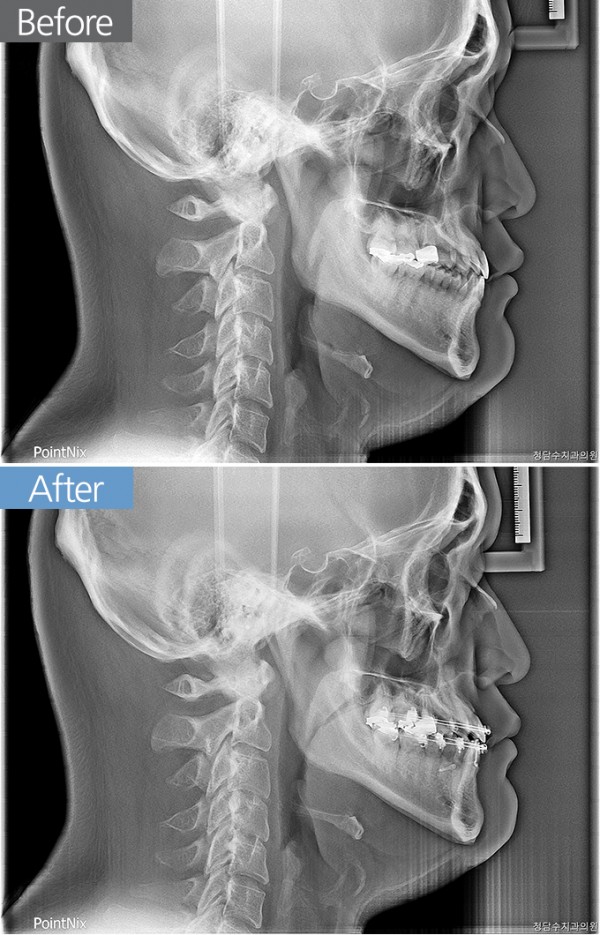

과잉치/왜소치교정